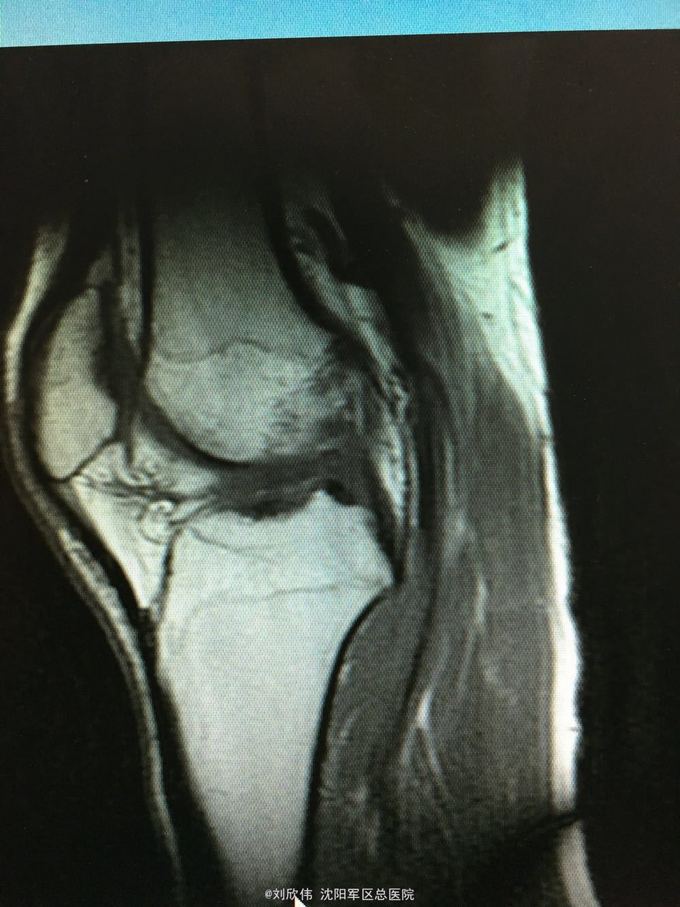

训练致右膝肿痛伴活动受限3个月 自觉脱臼感

右膝lachman试验,轴移试验阳性 MRI提示ACL已显示不清,半月板后角高信号(但术中未见撕裂,mri存在假阳性)

右膝前交叉韧带断裂 右膝半月板损伤 手术方法如题,直接上图

这个病例术后汇付的非常快 值得讨论的是acl重建时,股骨隧道内口的选择还是很有讲究的,目前从AM入路建立隧道点很热,但是,说是解剖重建,术中确实很多人选的点确是等长点,由于我们LARS韧带也做,所以这点体会有味深刻 解剖点的位置相比等长点,是比较偏下的(屈膝90°,关节镜操作时的角度而言),偏向平台关节面,这样虽然解剖,但会导致股骨隧道长度过短。需要注意